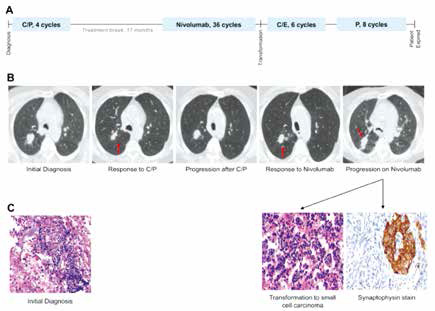

SCLC转化或为免疫治疗获得性耐药机制

SCLC转化或为免疫治疗获得性耐药机制

以色列Sheba医学中心Bar等报告,非小细胞肺癌(NSCLC)患者接受免疫检查点抑制剂(ICI)时,发生小细胞肺癌(SCLC)转化可能是获得性耐药的一种机制。初次缓解或混合缓解后进展病…